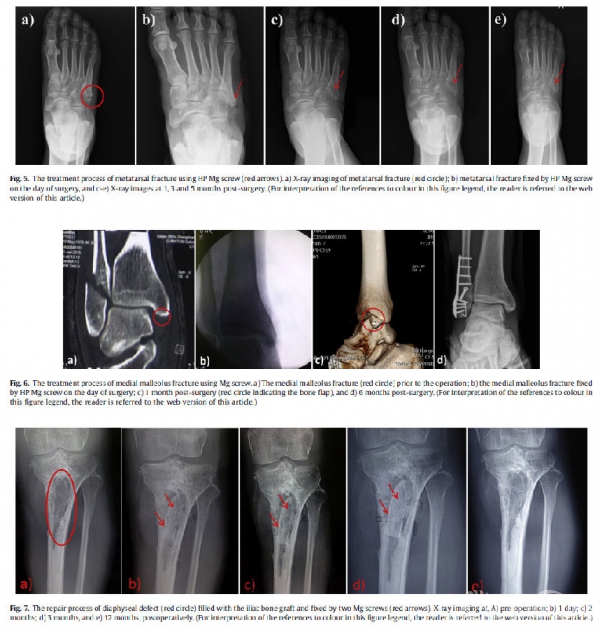

图4(fig 4-7). 镁金属在不同部位的临床应用

2013年,在中国,赵等使用专门设计的高纯Mg螺钉固定带血管蒂骨瓣治疗(ARCO)II/III期股骨头坏死。在12个月的随访期间,用高纯Mg螺钉固定移植骨瓣,取得更加令人满意的治疗结果(Mg组n=23,对照组n=25)(使用Harris髋关节评分(HHS)及x线片评估)。这是中国第一次临床试验,极大地促进了纯Mg基螺钉在ONFH重建手术中的应用,加速纯镁螺钉产品注册过程。这种HPMg螺钉的创新设计最近也被中国FDA(CFDA)在2015年评为创新医疗设备奖。这些治疗结果激励赵及其团队寻找不同骨折适应症的患者。详细的治疗结果总结在表3中作为参考和未来的系统性临床试验。

总的来说,截止目前,令人鼓舞的是,基于Mg的固定装置已经成功地应用于患者的一些低负重的骨折部位而没有负面的临床结果,这激励临床医生和学者考虑在其他适应症中使用基于Mg的装置。此外,另一个前景是开发新的含有镁植入物和传统的金属设备的混合系统,以修复高负重部位的骨折。最重要的是,由于基于Mg的矫形装置的研发涉及多学科,包括材料设计和制备、医疗装置设计和制造、生物评估、临床评估和产品注册,有必要在大学、研究所、医院之间建立合作平台和企业促进新型镁植入物的研发,以便在其产品进入市场前的临床前期及临床研究。